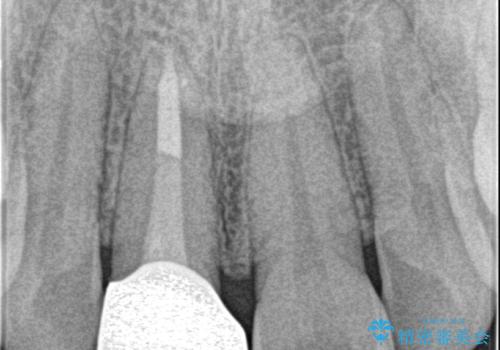

- 前歯が気になるとの事で来院。保険の被せ物(プラスチック素材)メタルの土台が入っていたので

拡大鏡下で全て除去し精密根管治療を行いセラミックの被せ物を装着しました。